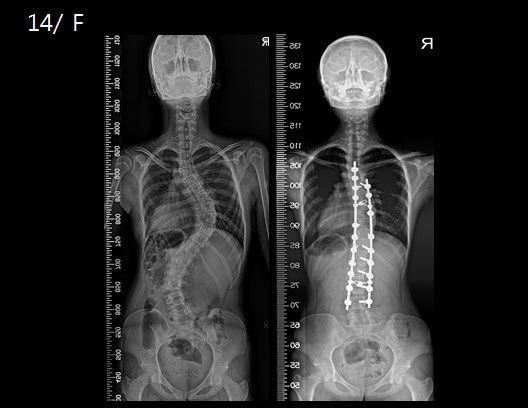

나는 척추측만으로 2001년 12월 8시간? 이상의 암튼 엄청 대수술을 진행했다.

위의 참고 사진 중 왼쪽 사진처럼 위아래가 거의 60도 이상의 만곡을 보이고

3년 정도의 보조기와 재활운동으로도 좋아질 기미가 없어 더 늦기 전에 수술을 단행한 것이다.

위 사진의 경우 수술 후 흉추와 요추가 모두 핀으로 잡힌 케이스지만

나는 적극적인 재활운동 덕분에 흉추만 잡아도 요추까지 같이 각도가 돌아올 것으로 예상해 다행히 수술 범위를 많이 좁힐 수 있었다.

하지만 역시나 수술 후유증?으로 흉추의 대부분을 제대로 사용할 수 없어 지금까지도 롤업, 싯업, 크런치, 쟁기자세 등과 같은 등을 말거나 굽혀하는 동작은 할 수 없거나 가동범위가 나오지 않는다.